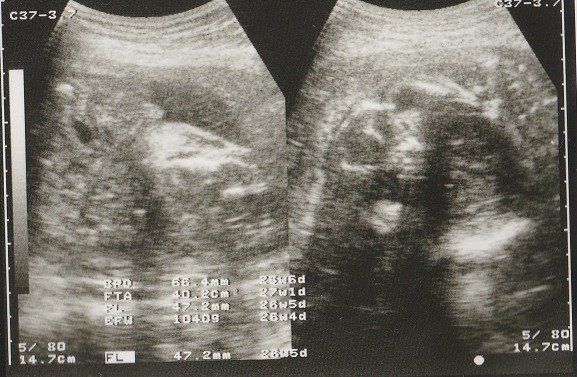

ちゃじゅびさんの妊娠26週目のエコー写真 男の子であることが判明

左側のエコー画像に、男の子のシンボルが写っています。人によっては、生まれるまで男の子か女の子か告げて欲しくないという方もいらっしゃるようですが、私の場合、お医者さんに何も聞かれずに「男の子ですね」と言われました。

左側は頭の画像。赤ちゃんの頭もだいぶ大きくなりました。